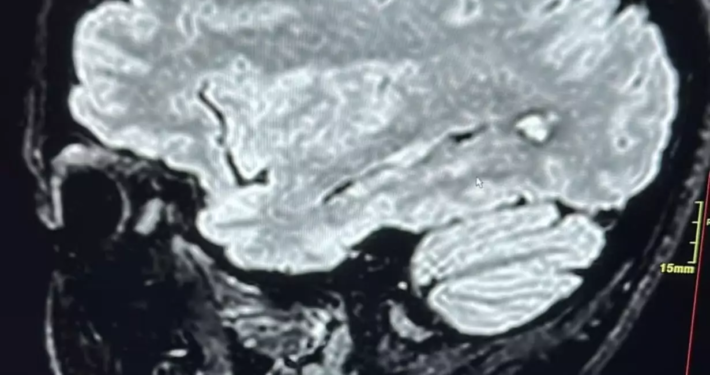

Cisti Neuroenterica dell’Encefalo: una diagnosi rara che rivela l’importanza dell’approccio multidisciplinare

La cisti neuroenterica dell’encefalo è una malformazione congenita…

Angioma cavernoso, quando l’acufene può salvarti la vita

L'angioma cavernoso è una patologia vascolare cerebrale rara,…